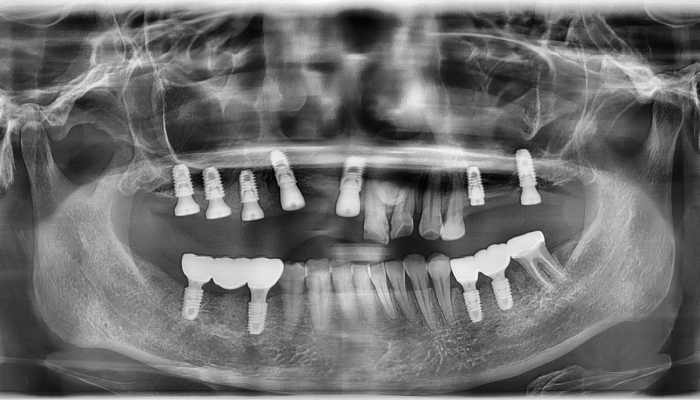

상악동거상술 전후 사례

• 식립전

식립후